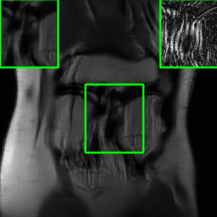

| Ground Truth | Vanilla MoDL | RS-E2E | SMUG |

![]() |

| PSNR = dB | PSNR = 23.41 dB | PSNR = 24.58 dB | PSNR = 28.91 dB |

| AT | Score-MRI | Deep-Equilibrium | Weighted-SMUG |

| PSNR = 28.67 dB | PSNR = 27.89 dB | PSNR = 24.13 dB | PSNR = 29.41 dB |

Results for the FastMRI Knee Dataset: In Fig 5 and Fig 7, we report PSNR and SSIM results of different methods at two sampling acceleration factors for the knee dataset. Therein, we observe quite similar outcomes to those reported in Fig 3. Figs. 6 and 8 show reconstructed images by different methods for knee scans at 4x and 8x undersampling, respectively. We observe that SMUG and Weighted SMUG show fewer artifacts, sharper features, and fewer errors when compared to Vanilla MoDL and other baselines in the presence of the worst-case perturbations.